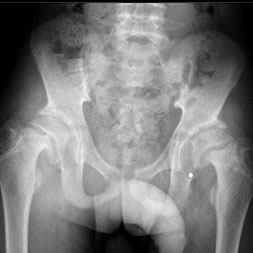

Proximal Femoral Growth Alterations Can Be Seen Prior to Treatment of Developmental Dysplasia of the Hip: A Multicenter Cohort Study

Patrick England, Emily Schaeffer, Charles Price, Kishore Mulpuri, Global Hip Dysplasia Registry (GHDR), Wudbhav N. Sankar